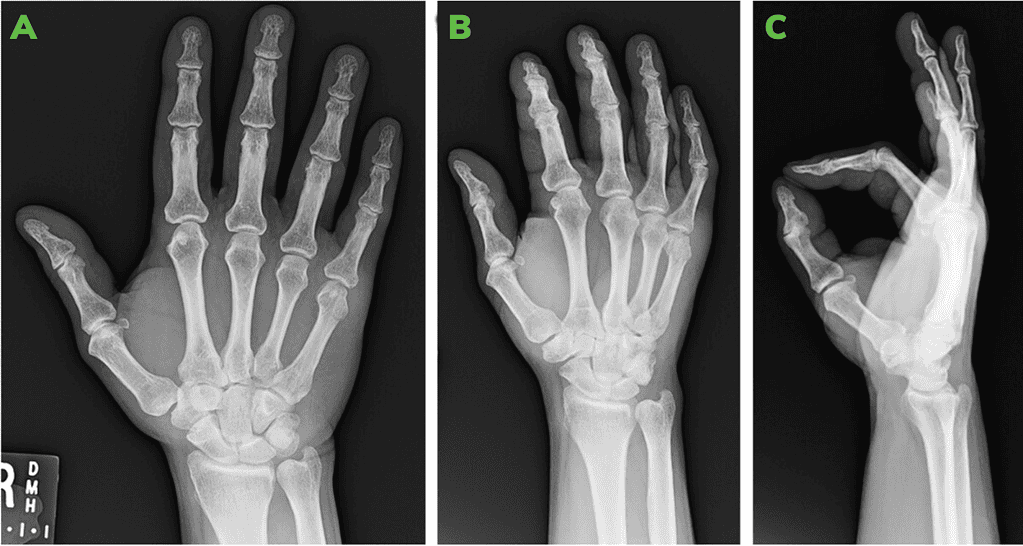

Pre-Operative X-Rays Showing 5Th Metacarpal Neck Fracture: Ap [A] Oblique [B] And Lateral [C]

Figure 1: Pre-operative X-rays showing 5th metacarpal neck fracture: AP [A] Oblique [B] and Lateral [C]